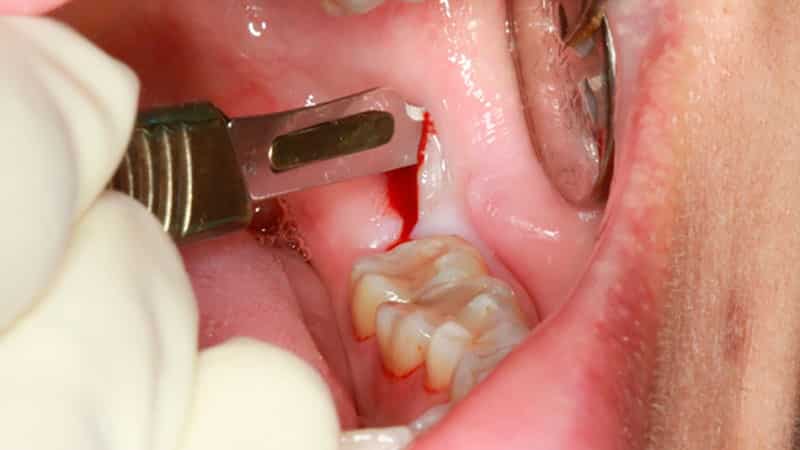

Процедура удаления зубов мудрости является сложной и особенной. Хирург использует специальные щипцы с незакрывающимися щеками для оперативного вмешательства. Пациенту вводится анестезия, после чего врач делает надрез на десне и высверливает небольшую лунку в костных тканях.

Если необходимо, зуб может быть распилен стоматологическим диском или бором. После этого специалист помещает лекарственное средство в альвеолярное отверстие и зашивает его. Такая операция является безопасным способом, который снижает риск повреждения слизистой оболочки, соседних зубов и костных тканей.